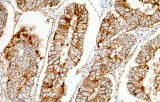

Primary antibodies for immunohistochemistry CE/IVD - Cytopathology

Cytopathology is a branch of pathology that studies and diagnoses diseases on the cellular level. Cytopathology is the use of specialist diagnostic techniques to examine individual cells extracted from tissues to determine the cause and nature of a disease.

Cytopathology is commonly used to investigate diseases involving a wide range of body sites, often to aid in the diagnosis of cancer, but also in the diagnosis of some infectious diseases and other inflammatory conditions. For example, a common application of cytopathology is the Pap smear, a screening tool used to detect precancerous cervical lesions which may lead to cervical cancer.